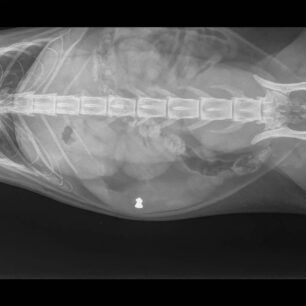

Οι ακτινογραφίες έδειξαν ότι η γάτα έπεφτε για δεύτερη φορά θύμα κάποιου αδίστακτου ανθρώπου καθώς ακόμα ένα σφαιρίδιο αεροβόλου ήταν καρφωμένο στην κοιλιά της και αυτό πρέπει να είχει γίνει παλιότερα.

Κατά τη διερεύνηση του περιστατικού βγάλαμε ακτινογραφίες και λυπημένοι και σοκαρισμένοι διαπιστώσαμε ότι το ζώο είχε τραυματιστεί με σκάγια αεροβόλου όπλου και μάλιστα δεν ήταν πρώτη φορά αφού βρέθηκε και ένα σκάγι στην κοιλιακή χώρα από παρελθόντα χρόνο.

4η και 5η φωτογραφία ακτινογραφίες κοιλιάς της γάτας που φαίνεται το παλιό σκάγι